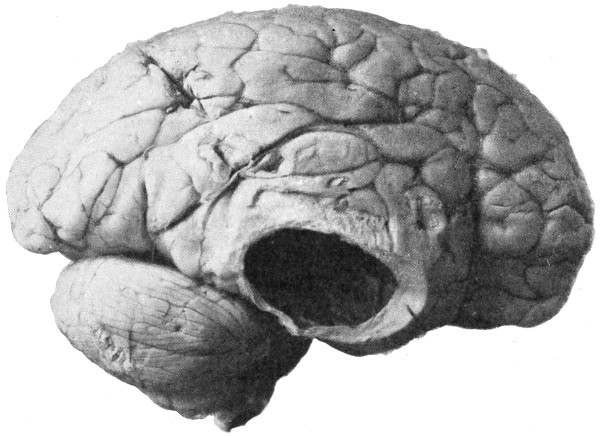

Fig. 20. An Occipital Cephalocele. (For further description, see text.)

1. Occipital cephaloceles—the commonest variety—occupy, anatomically, two positions (1) between the two lower segments of the occipital bone (inferior occipital cephaloceles), often involving the foramen magnum and sometimes complicated by a condition of cervical spina bifida, and (2) between the two upper segments of the occipital bone (superior occipital cephaloceles), occasionally involving the posterior fontanelle.

The tumour may possess a broad base or may be definitely pedunculated. In the former instance the gap in the bone may be of considerable size and the margins everted: in the latter case, the hole may be quite small.

The deformity is frequently associated with other congenital defects—hydrocephalus, microcephalus, spina bifida, hare lip, hernia, and talipes.

Sincipital cephaloceles are usually quite small, but the occipital variety and those situated in[35] the region of the anterior fontanelle frequently attain a great size (see Figs. 20-22).

Fig. 22. An Occipital Cephalocele. (For further description, see text.)

The child was 3 months old, and presented a tumour, the size of an orange, situated between the occipital protuberance and the nape of the neck. The mass was pedunculated, the stalk being about the size of a four-shilling piece in diameter. It was soft, translucent, irreducible, and swelled up on coughing. An attempt at removal was carried out, and, after incising the outermost layers, three ounces of cerebro-spinal fluid escaped. A second tumour was then found occupying the base of the swelling. This was also punctured, more fluid escaping. Both sacs were cut away and the wound sewn up. Death occurred on the third day, preceded by convulsions, retraction of the head and neck, and high fever. The autopsy showed that the fontanelles were widely open, the anterior measuring 4 inches from side to side and 21⁄2 from before backwards. The bones of the vault were markedly thinned. In the subdural space there was a quantity of fluid, and the cerebral substance was soft and diffluent, the convolutions flattened, and the ventricles distended. There was a broad gap in the occipital bone, extending downwards into the foramen magnum, and in this situation the cerebellum had bulged backwards into the protruding mass. (See Fig. 22).